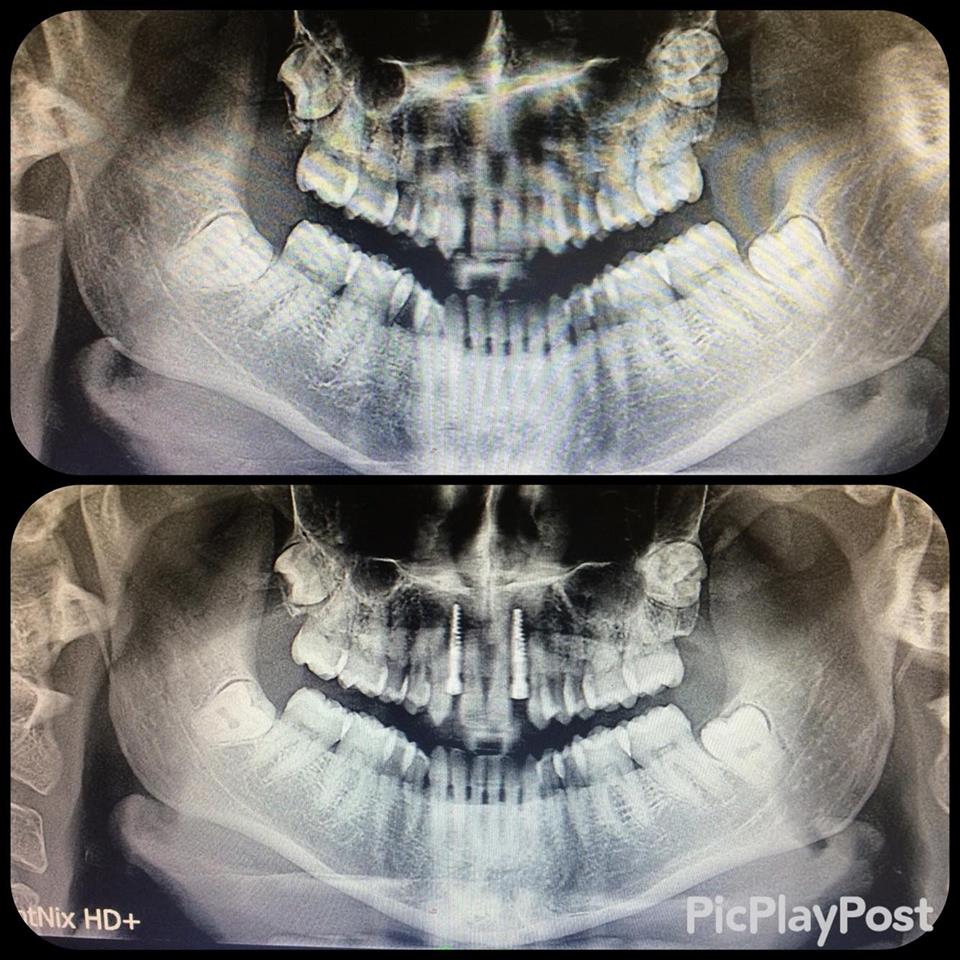

İMPLANT TEDAVİSİ

implant tedavisi